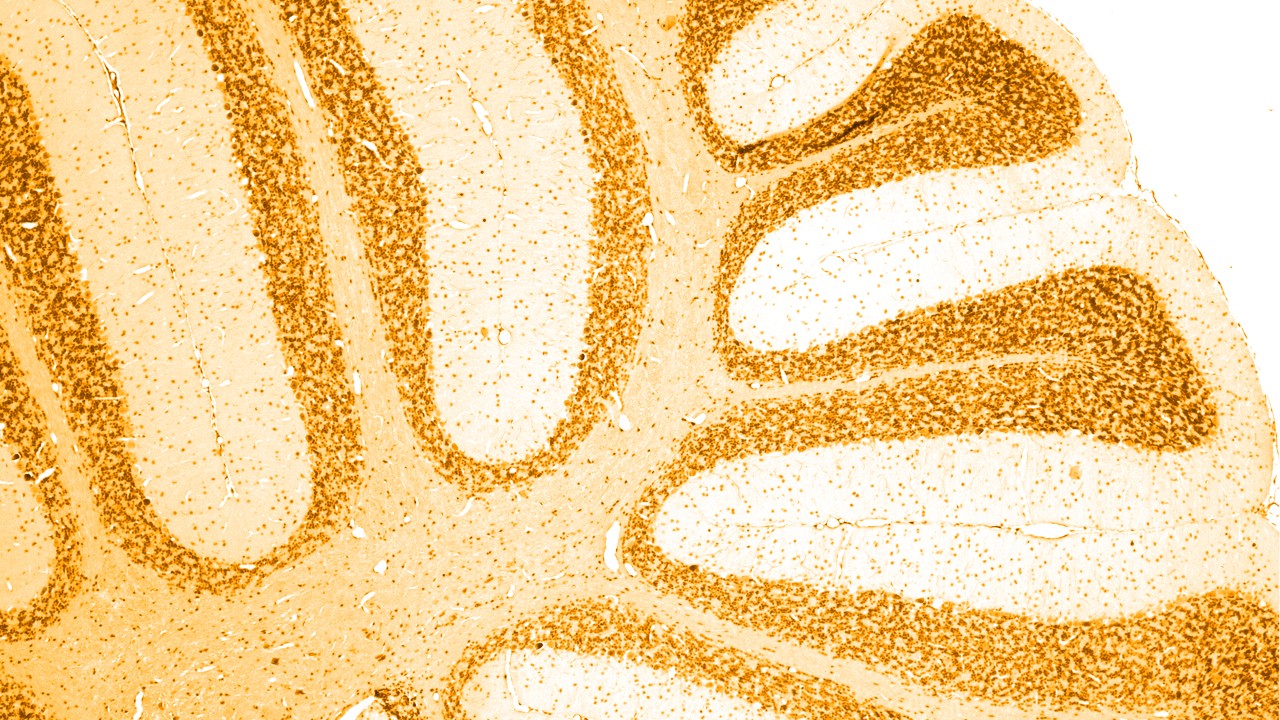

![自律神経失調症[不安神経症 運動神経型]](https://ohishiheal.net/wp/wp-content/uploads/2014/05/undousinkei.jpg)